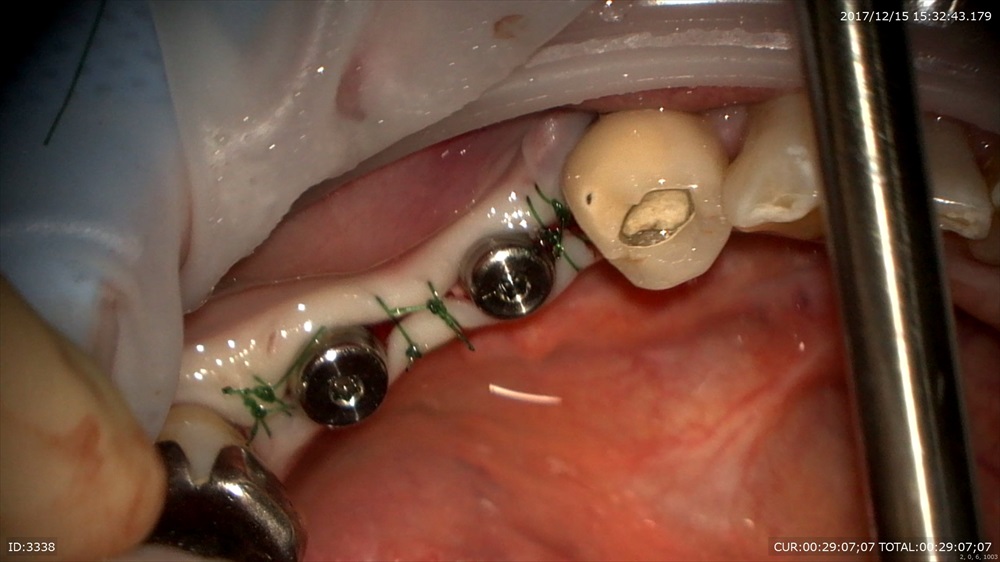

インプラントのOPEから。最初は怖がっていましたが全然痛くないと喜んで頂けました。

「緊張して損した」

と嬉しいお言葉を頂きました。痛みだけではなく腫れや出血をなくすため事前の準備とマイクロスコープを使ったオペは必須だと思います。治療も一回法を選択でき何回もオペをせずに歯がはいります。1回で終わります。この方もセカンドオピニオンで来院されました。